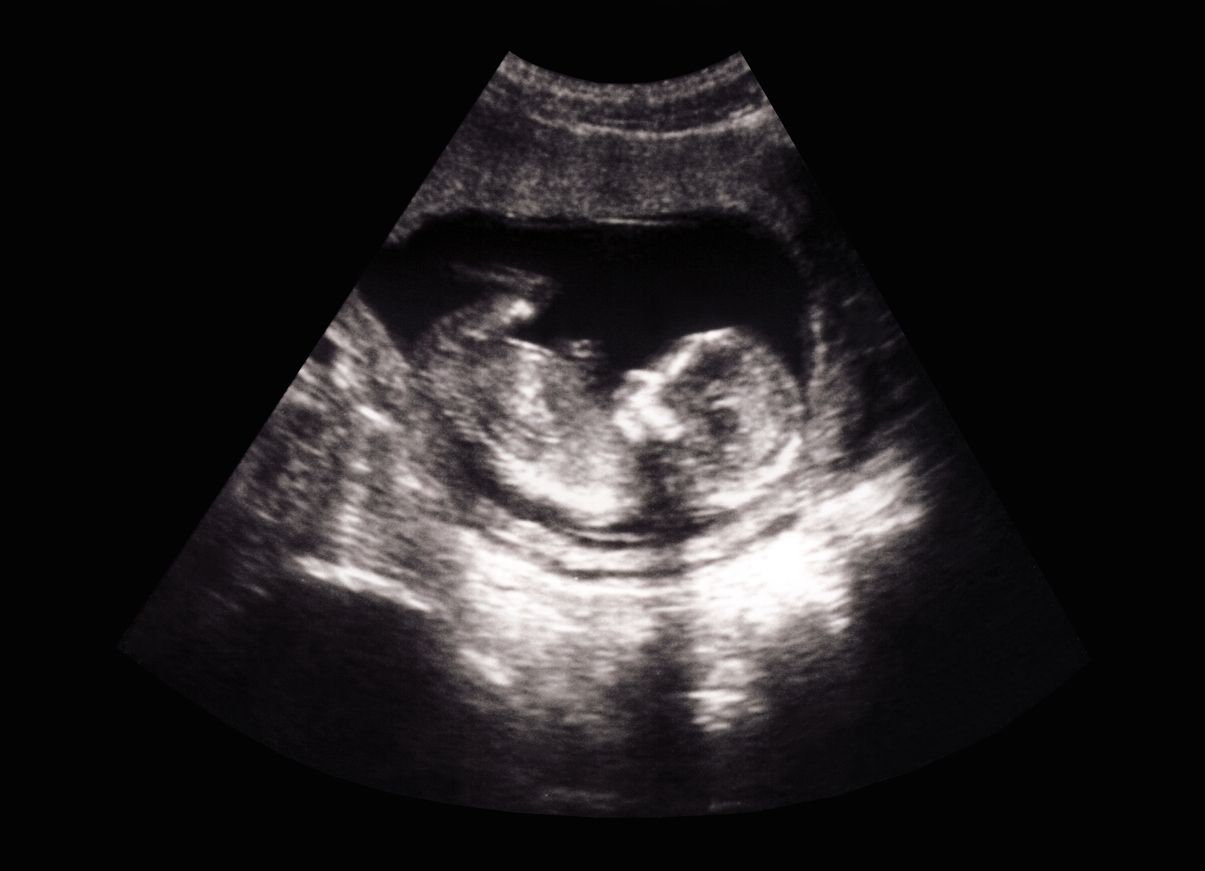

Der Zugang zu Abtreibungspillen soll damit für Frauen erleichtert werden.

Getty Images (Symbolbild)